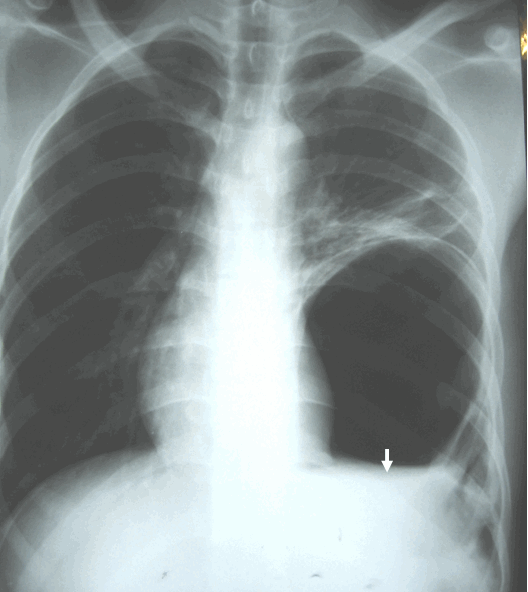

Hình ảnh thoát vị hoành trái trên phim chụp phổi thẳng có mức nước mức hơi giống hình ảnh của áp xe phổi trái

Hình ảnh thoát vị hoành (thoát vị dạ dày) có mức mức hơi giống áp xe phổi ở bệnh nhân nam, 21 tuổi